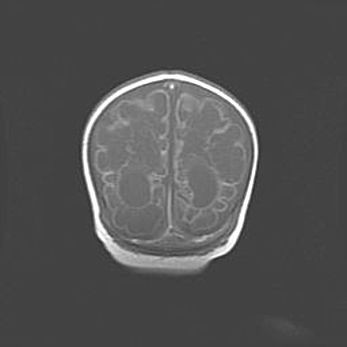

Церебральная ишемия II.

Возраст: 5 дней

Вес: 3400 г

Пол: женский

Окружность головы: 35 см

Срок гестации: 39 недель

Церебральная ишемия – это заболевание, характеризующееся недостаточностью (гипоксией) либо полным прекращением (аноксией) снабжения мозга кислородом по причине закупорки одного или нескольких сосудов. Это приводит к  что метаболическим расстройствам различной степени тяжести в тканях головного мозга, развитию коагуляционных некрозов и гибели нейронов.